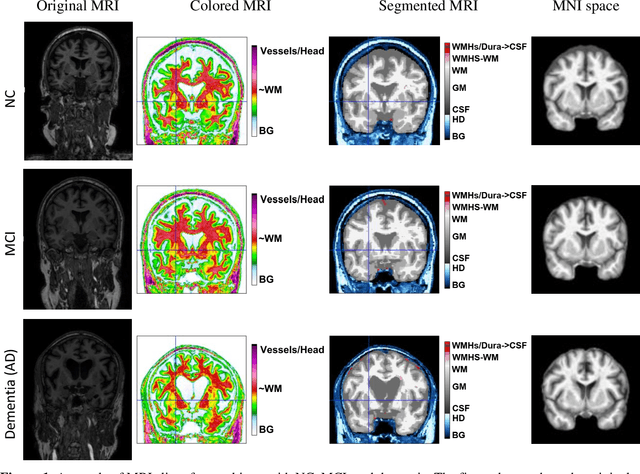

Abstract:Now that disease-modifying therapies for Alzheimer disease have been approved by regulatory agencies, the early, objective, and accurate clinical diagnosis of AD based on the lowest-cost measurement modalities possible has become an increasingly urgent need. In this study, we propose a novel feature extraction method using persistent homology to analyze structural MRI of the brain. This approach converts topological features into powerful feature vectors through Betti functions. By integrating these feature vectors with a simple machine learning model like XGBoost, we achieve a computationally efficient machine learning model. Our model outperforms state-of-the-art deep learning models in both binary and three-class classification tasks for ADNI 3D MRI disease diagnosis. Using 10-fold cross-validation, our model achieved an average accuracy of 97.43 percent and sensitivity of 99.09 percent for binary classification. For three-class classification, it achieved an average accuracy of 95.47 percent and sensitivity of 94.98 percent. Unlike many deep learning models, our approach does not require data augmentation or extensive preprocessing, making it particularly suitable for smaller datasets. Topological features differ significantly from those commonly extracted using convolutional filters and other deep learning machinery. Because it provides an entirely different type of information from machine learning models, it has the potential to combine topological features with other models later on.

Abstract:Alzheimer's disease (AD) is a neurodegenerative disorder affecting millions worldwide, necessitating early and accurate diagnosis for optimal patient management. In recent years, advancements in deep learning have shown remarkable potential in medical image analysis. Methods In this study, we present "ViTranZheimer," an AD diagnosis approach which leverages video vision transformers to analyze 3D brain MRI data. By treating the 3D MRI volumes as videos, we exploit the temporal dependencies between slices to capture intricate structural relationships. The video vision transformer's self-attention mechanisms enable the model to learn long-range dependencies and identify subtle patterns that may indicate AD progression. Our proposed deep learning framework seeks to enhance the accuracy and sensitivity of AD diagnosis, empowering clinicians with a tool for early detection and intervention. We validate the performance of the video vision transformer using the ADNI dataset and conduct comparative analyses with other relevant models. Results The proposed ViTranZheimer model is compared with two hybrid models, CNN-BiLSTM and ViT-BiLSTM. CNN-BiLSTM is the combination of a convolutional neural network (CNN) and a bidirectional long-short-term memory network (BiLSTM), while ViT-BiLSTM is the combination of a vision transformer (ViT) with BiLSTM. The accuracy levels achieved in the ViTranZheimer, CNN-BiLSTM, and ViT-BiLSTM models are 98.6%, 96.479%, and 97.465%, respectively. ViTranZheimer demonstrated the highest accuracy at 98.6%, outperforming other models in this evaluation metric, indicating its superior performance in this specific evaluation metric. Conclusion This research advances the understanding of applying deep learning techniques in neuroimaging and Alzheimer's disease research, paving the way for earlier and less invasive clinical diagnosis.

Abstract:Alzheimer's is a brain disease that gets worse over time and affects memory, thinking, and behavior. Alzheimer's disease (AD) can be treated and managed if it is diagnosed early, which can slow the progression of symptoms and improve quality of life. In this study, we suggested using the Visual Transformer (ViT) and bi-LSTM to process MRI images for diagnosing Alzheimer's disease. We used ViT to extract features from the MRI and then map them to a feature sequence. Then, we used Bi-LSTM sequence modeling to keep the interdependencies between related features. In addition, we evaluated the performance of the proposed model for the binary classification of AD patients using data from the Alzheimer's Disease Neuroimaging Initiative (ADNI). Finally, we evaluated our method against other deep learning models in the literature. The proposed method performs well in terms of accuracy, precision, F-score, and recall for the diagnosis of AD.